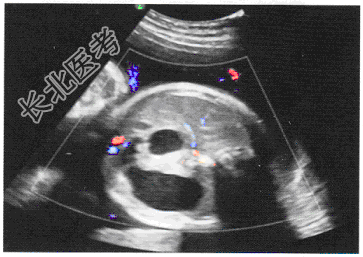

- 单项选择题患者,女, 30岁,孕28周, 胎儿超声检查如图,以下最可能的诊断是

A、十二指肠闭锁

B、食管闭锁

C、肾积水

D、肛门闭锁

E、淋巴管囊肿